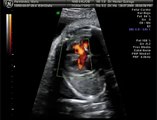

¿Tetralogía de Fallot? Conoce esta malformación congénita del corazón

¿Qué es la te­tra­lo­gía de Fa­llot? La te­tra­lo­gía de Fa­llot es una mal­for­ma­ción con­gé­ni­ta que se ca­rac­te­ri­za por­que la o el pa­cien­te pre­sen­ta cua­tro ano­ma­lías en el co­ra­zón.